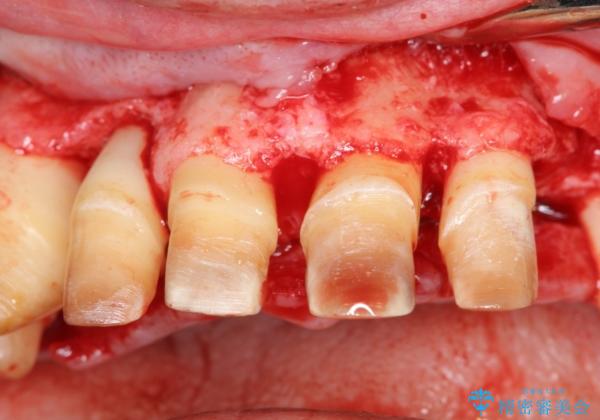

上顎は、残っている前歯も揺れがあり残すためにはクラウンでつなぐ歯周補綴が必要な状態です。

また咬合負担に不安のある前歯を助けるためにも、臼歯部にインプラント補綴を行いしっかりとかめる状態とすることも大切です。